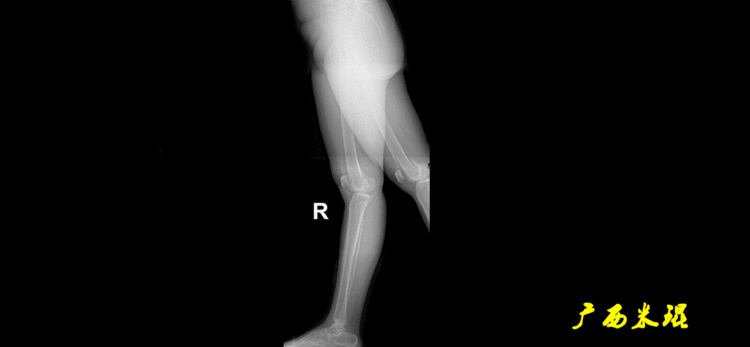

下肢力线及相关角度测量的前提是必须拍摄标准的站立位也就是负重位的下肢全长片。目前这样的照片都是放射科的技师在电脑上拼接出来的,大部分医院的DR都能够做到这一点。

患者直立于摄影架上,后背贴近摄影架,双手自然下垂,膝关节尽量伸直,足部与双肩同宽,要求投照时双髌骨朝正前方,通常患者双足尖应平行向前即可。

提醒一下大家,拍摄过程中应避免下肢的外旋和内旋。如果有一侧肢体短缩时,投照应当用脚垫垫高短缩肢体,使骨盆保持水平,这样下肢短缩测量才精确。如果有肢体旋转畸形时,还是以髌骨朝前为标准,虽然此时双足可能不能保持平行。

下肢全长片的基本要求

无论如何,拍摄出来的下肢全长片必须包含髋关节中心、膝关节中心及踝关节中心,否则对临床是无用的。有了一张下肢的全长照片,我们需要确定下肢关节的中心点,通过中心点画出下肢的各种轴线,然后利用轴线与关节线的相交得出各种所需要的角度。